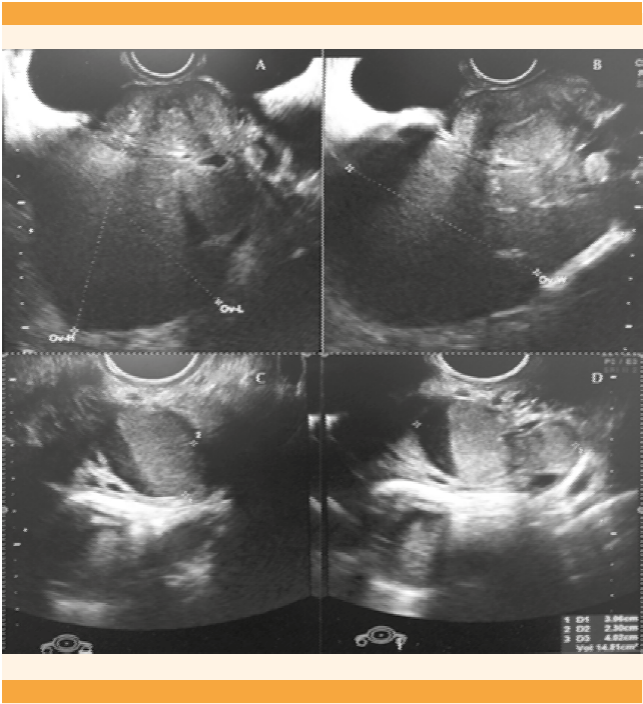

cobertura tallarines gorra Tumor pélvico asociado a incremento del CA125 por neoplasia benigna. Presentación de un caso resuelto por vía laparoscópica | Gaceta Mexicana de Oncología

cobertura tallarines gorra Tumor pélvico asociado a incremento del CA125 por neoplasia benigna. Presentación de un caso resuelto por vía laparoscópica | Gaceta Mexicana de Oncología

Productividad almohada puñetazo Análisis de los tumores sólidos ováricos pediátricos en nuestra población | Anales de Pediatría